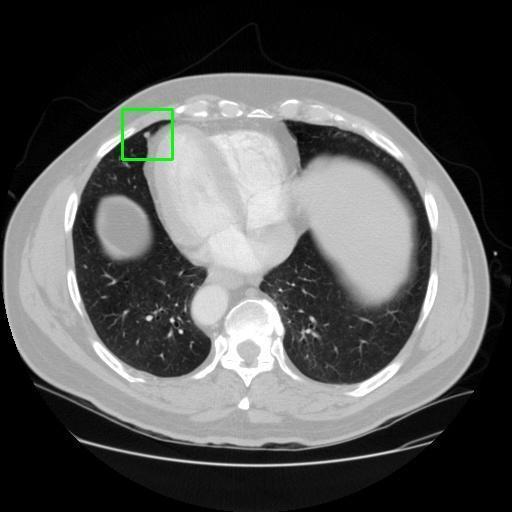

We developed an AI-based system using deep learning models for analyzing lung CT scans to detect and classify pulmonary nodules. We chose the YOLOv11 architecture for its enhanced object detection capability and adapted it specifically for medical imaging, incorporating pixel-level precision and severity classification.

Classification into three severity levels with colored bounding boxes.

Designed a severity classification system that categorizes nodules into null, moderate, and severe using colored bounding boxes, assisting in rapid clinical decision-making.